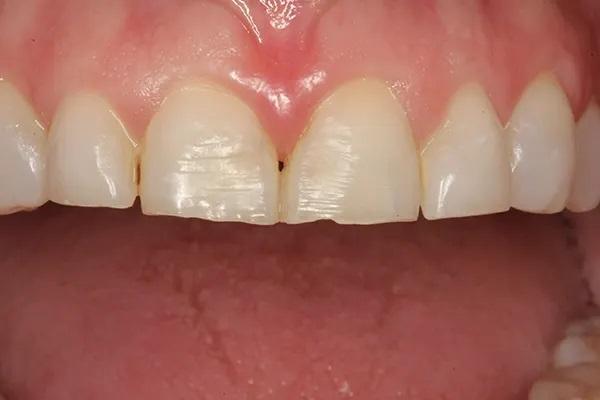

35-летняя пациентка женского пола, наблюдаясь у своего стоматолога с детства выразила заинтересованность в улучшении внешнего вида своих передних зубов, которые в свою очередь, имеют значительные дефекты твёрдых тканей и сколы. Вид улыбки пациентки до лечения "во все зубы" (фото 1); При большом приближении видны сколы во фронтальном отделе зубных рядов (фото 2) Горизонтальный тип стираемости зубов на верхней челюсти (фото 3.). Ее история болезни была отмечена Американским обществом анестезиологов (ASA) II, ввиду ее непереносимости к анестетикам, тем не менее она успешно лечилась с применим препарата Диован. В остальном ее соматическое здоровье никак не отражалось на стоматологическом лечении. В стоматологическом анамнезе у пациенты были выполнены ресторации отдельных зубов и удаление зубов мудрости в подростковом возрасте Представлены прицельные снимки зубов перед восстановительным лечением (фото 4). Также она проходила стоматологическое лечение ранее в детстве. Ее больше всего беспокоил неприглядный вид фронтальных зубов со сколотыми неровными краями на всем протяжении от моляров до первых резцов.

Фото 2